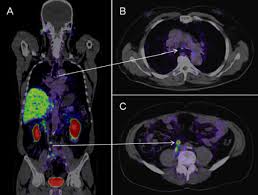

여기에 방사성 핵종 F-18를 붙여(F-18 FDG라고 함) 혈관 주사하면 빨리 자리는 암세포는 포도당이 더 필요해 정상 세포보다 10∼100배 더 많이 모여들고 이를 방사능으로 촬영해 찾아낸다. 암이 1㎝만 돼도 10조개의 암세포가 있어 CT, MRI 소견이 애매한 경우 유용하게 쓰인다.

물론 PET도 아주 작은 암은 놓치기도 하지만 대체로 약 0.5㎝ 이상의 암은 거의 80% 찾아내고 있다고 한다.

PET의 또 다른 장점으로 거의 모든 종류의 암을 찾아낼 수 있다는 것이라고 한다. 일반적으로 암세포는 포도당 대사가 높기 때문이라고 한다.

그러나 일본의 경우 증상이 없는 PET 검진자의 1∼2%에서 암을 찾아내고 있다고 한다. 또 이미 암을 진단받은 후에도 전신 PET를 해 보면 5∼7%에서 숨어 있는 다른 암을 찾을 수 있다고 한다.

물론 고령의 할아버지와 할머니가 많지만 우리나라 남자의 3분의1에서 2분의1이 일생동안 결국은 암에 걸린다는 통계자료를 볼 때 수긍이 된다. 일본 자료에 의하면 갑상선암, 폐암, 대장암 등이 잘 발견되고 있다고 한다.